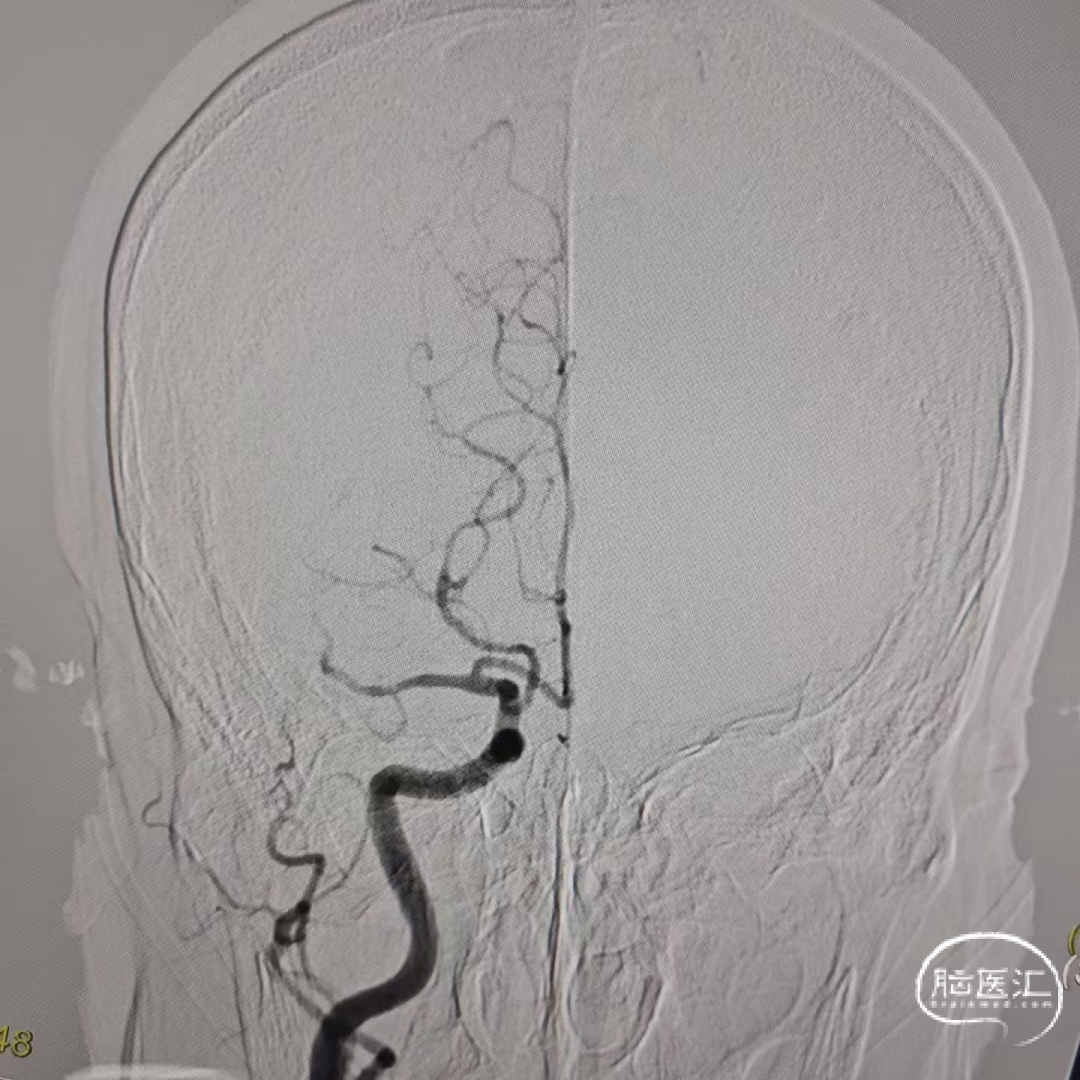

SWIM技术抽拉一次去除微量血栓,造影提示左侧大脑中动脉及以远动脉早、中、晚期血流速明显恢复正常。

术后3D造影右侧大脑中动脉M1段末段未见明显狭窄,考虑为血栓事件。

2015年多项试验(MR CLEAN、ESCAPE、SWIFT PRIME、REVASCAT和 EXTEND IA)证实了血管内机械取栓术在治疗前循环大血管闭塞卒中方面优于药物治疗,2017年,DAWN和DEFUSE-3试验成功地将患者的时间窗延长至24小时[1]。患者为发病15小时入院,已超溶栓时间窗,通过CTP可见右侧大脑半球CBF、MTT、TMax延长,CTA未见明显狭窄,故考虑行脑动脉造影术明确责任血管,脑动脉造影术中发现右侧大脑中动脉M1末段以远动脉早期、中期、晚期血流速减慢,与家属沟通后,尝试SWIM技术抽拉一次,可见微量血栓,后造影提示右侧大脑中动脉及以远动脉早期、中期、晚期血流速明显恢复正常;3D造影未见明显狭窄,考虑为血栓事件。